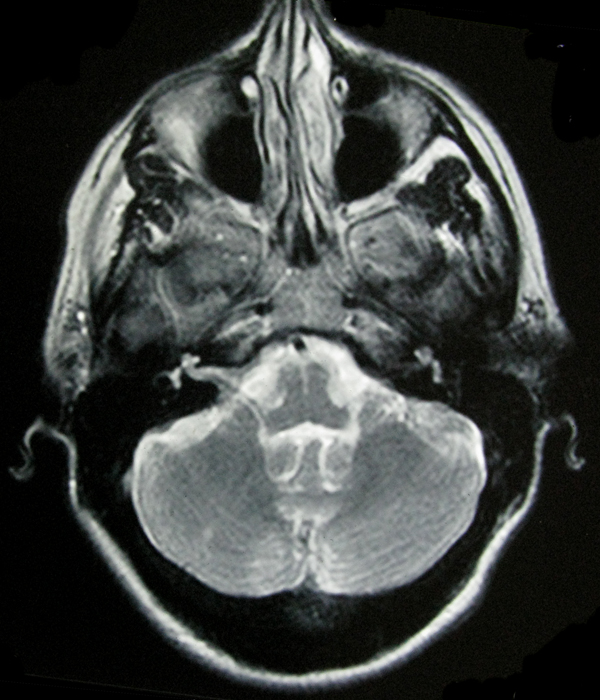

- My Brain in 2009